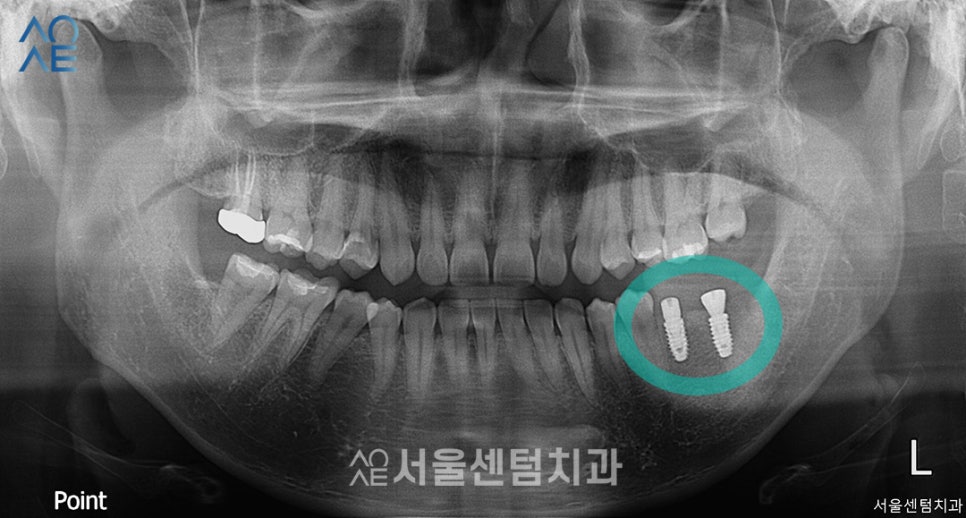

이제 왼쪽 아래에 임플란트까지 식립 후

촬영한 엑스레이입니다.

2개 모두 일체형으로 식립했기 때문에

2차수술은 필요하지 않았고

잇몸이 충분히 아무는 시간을 가지도록 했습니다.

임플란트까지 완성된 모습입니다.

이 분의 경우엔 잇몸뼈가 충분히 있었기에

뼈이식은 진행하지 않았습니다.

식립은 정확한 방향으로 안정적으로 잘 되었고

보철물 수복 역시 문제없이 마무리 되었습니다.